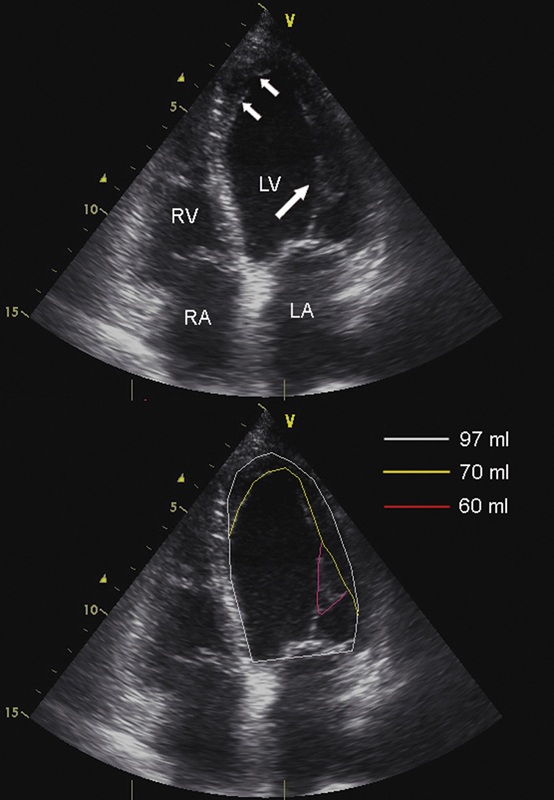

فحوصات تشخيصية لبعض امراض القلب والشرايين التاجية